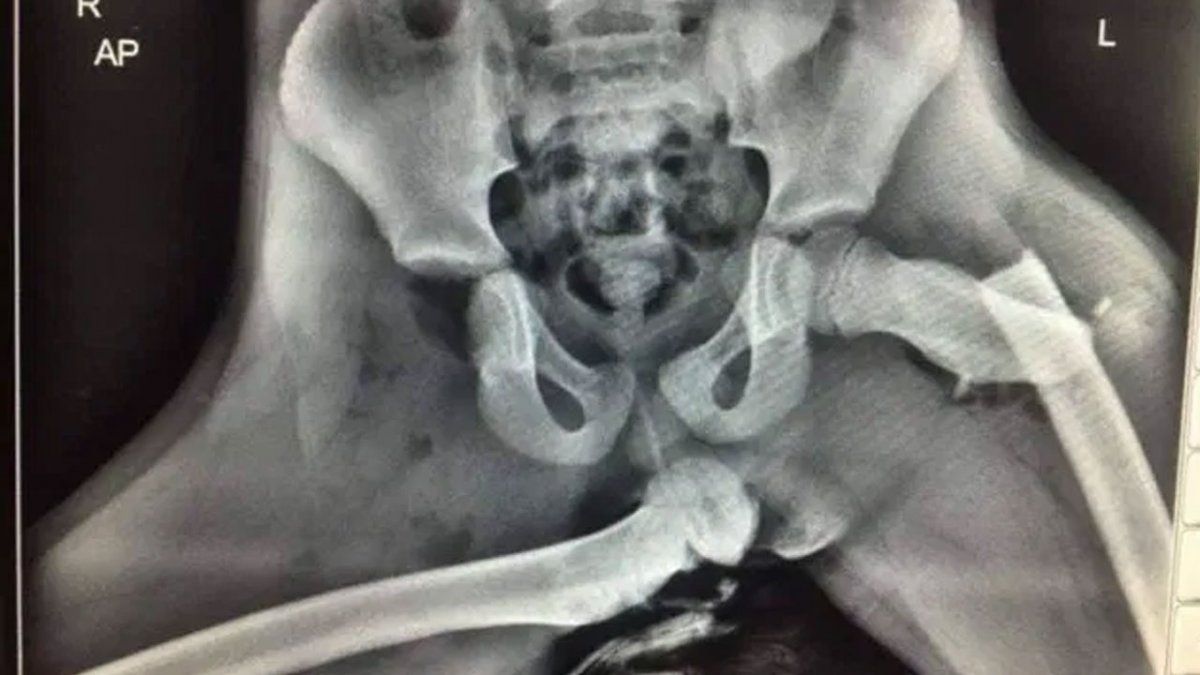

“Aquí hay una radiografía de horribles lesiones sufridas al pasajero del asiento delantero que tenía los pies en el tablero de instrumentos en el momento de una colisión. Si ve que su pasajero lo hace, deje de conducir y muéstrele esto”, escribió junto a una radiografía de una cadera con una pierna dislocada.

Actualmente no se sabe en qué condiciones se encuentra la mujer que sufrió la grave lesión en su cadera ahora. Pero, de acuerdo con el Daily Mail, las lesiones son tan severas que van a cambiar su vida para siempre, probablemente no va a volver a caminar bien.